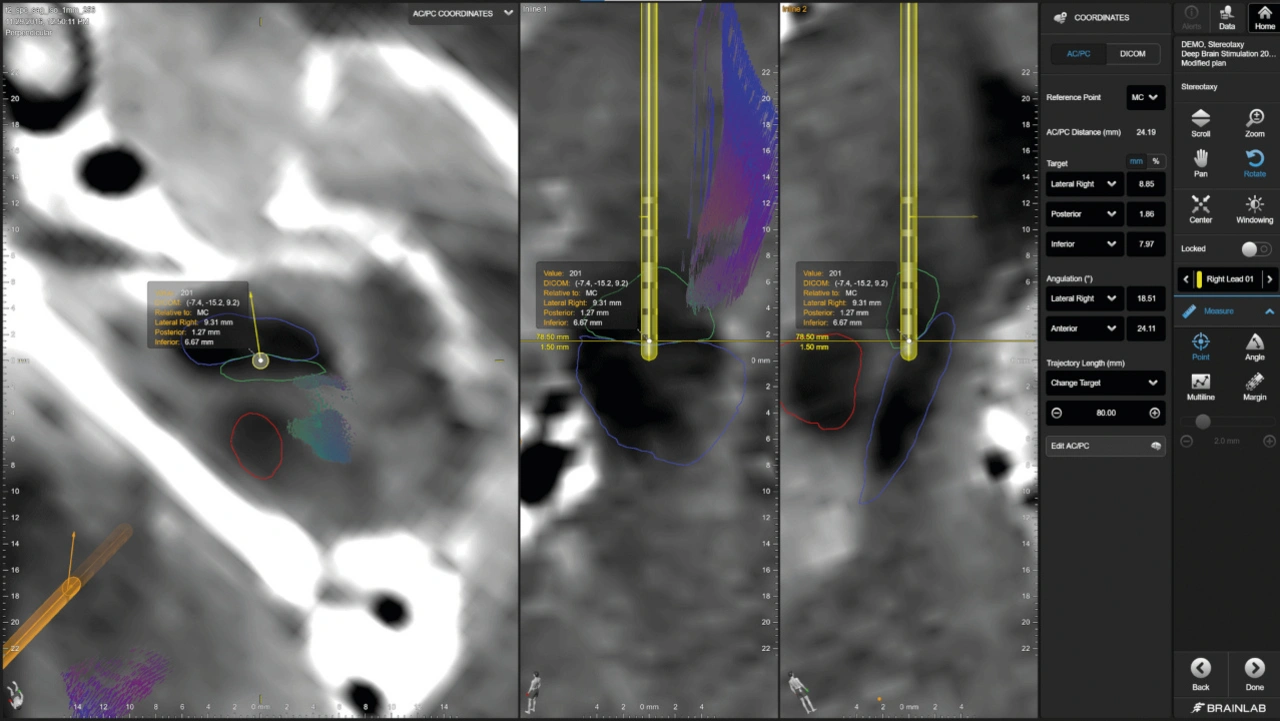

Bild 2. Dank der 3D-Visualisierung der Elektrodengeometrie, der automatisierten Elektrodenerkennung und der direktionalen Schätzung der Elektrodenausrichtung mittels Boston Scientific Vercise Cartesi-Richtelektroden ist es möglich, die genaue Platzierung von DBS-Elektroden zu ermitteln, so das Ziel exakt anzusteuern und eine genaue Patientenprogrammierung sicherzustellen.

Nachdem ChirurgInnen den Zielbereich im Gehirn als Startpunkt definiert haben, erfolgt die Trajektorienplanung: Mithilfe von 2D- und 3D-Visualisierung sowie flexibler 3D-Elektrodenmodellierung simuliert sie die geplante Trajektorie, um die Sicherheit des Eingriffs zu gewährleisten und mögliche Komplikationen zu minimieren.

Nach Abschluss der präoperativen Planung beginnt der intraoperative Teil des DBS-Verfahrens – ein kritischer Moment, in dem die zuvor virtuell geplante Strategie in die klinische Realität überführt wird. Mobile intraoperative Bildgebungssysteme unterstützen beispielsweise die stereotaktische Rahmenlokalisierung. Spezialisierte Softwarelösungen fusionieren Bilddaten in Echtzeit mit den präoperativ geplanten Modellen. Anhand von entweder intraoperativ aufgenommenen 3D- oder 2D-Aufnahmen können die implantierten Elektroden automatisch visualisiert und als 3D-Elektrodenformen modelliert werden, sodass medizinische Fachkräfte ihre akkurate Positionierung noch während der OP überprüfen können.